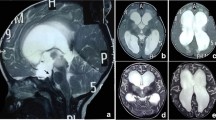

Pre-, 3-months and failure mid-sagittal CISS* magnetic resonance images of a 2 years old patient, who showed a preoperative Heidelberg score of + 2 (TVF** + 1 and LT*** + 1) (A), postoperatively 3 months later, the Heidelberg score went to -1 (TVF -1 and LT 0) (B), after 9 months, the patient showed hydrocephalic symptoms again and the Heidelberg score increased to + 2 (TVF + 1 and LT + 1) (C). 1 year after Re-ETV score dropped back to -1 (TVF -1 and LT 0) (D). *Constructive interference in steady state ** Third ventricle floor ***Lamina terminals